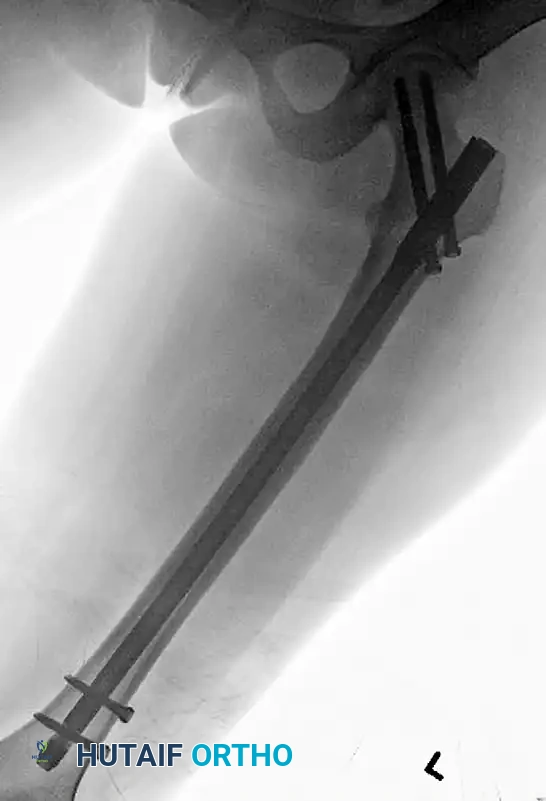

Image

Postoperative lateral radiograph confirming central placement of the cephalomedullary screws within the femoral head.